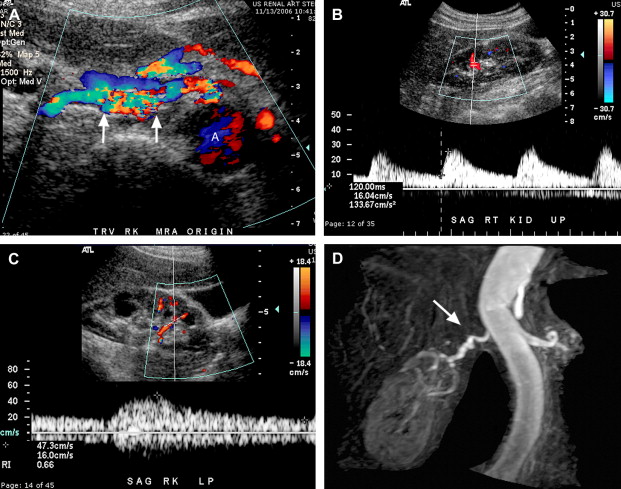

- Siêu âm Doppler động mạch tử cung: Phương pháp này giúp xác định tình trạng phát triển của thai nhi bằng cách đo lưu lượng máu qua động mạch tử cung, từ đó phát hiện dấu hiệu chậm phát triển do thiếu dinh dưỡng.

- Siêu âm Doppler động mạch rốn: Bác sĩ chỉ định siêu âm này để đánh giá sự phát triển của thai nhi, đặc biệt là trong trường hợp mẹ mang đa thai. Kỹ thuật này cũng đo lưu lượng máu qua dây rốn để kiểm tra sự tương thích giữa kháng thể Rh trong máu mẹ và thai nhi.

- Siêu âm Doppler động mạch não giữa: Siêu âm này sẽ cung cấp thông tin chi tiết về tình trạng sức khỏe của thai nhi nếu kết quả từ siêu âm động mạch rốn không bình thường. Bác sĩ sẽ tư vấn và điều trị nếu phát hiện thai nhi bị thiếu oxy hoặc dinh dưỡng.